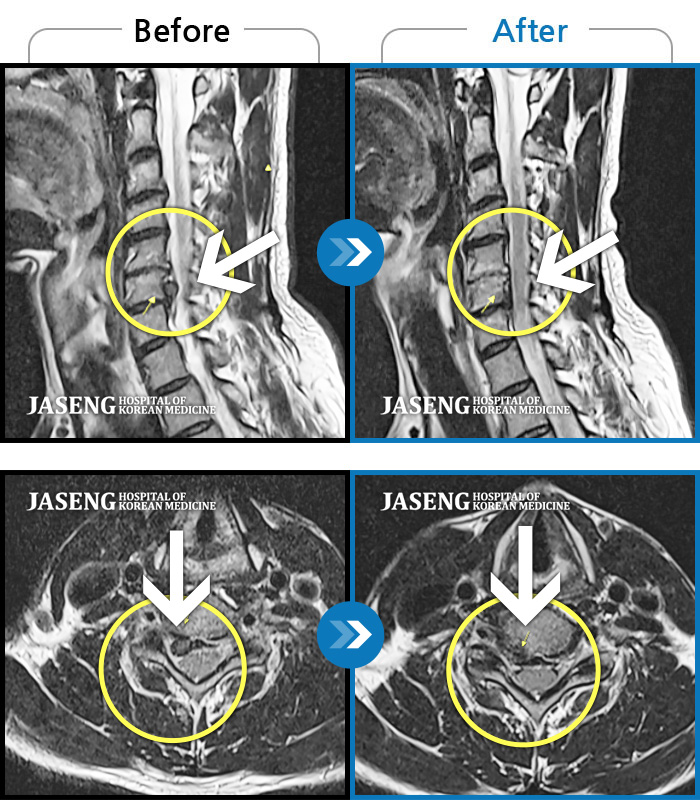

Before

After

목디스크로 인한 목통증 및 간헐적 손바닥 저림 증상

2018.10.02 ~ 2018.10.02